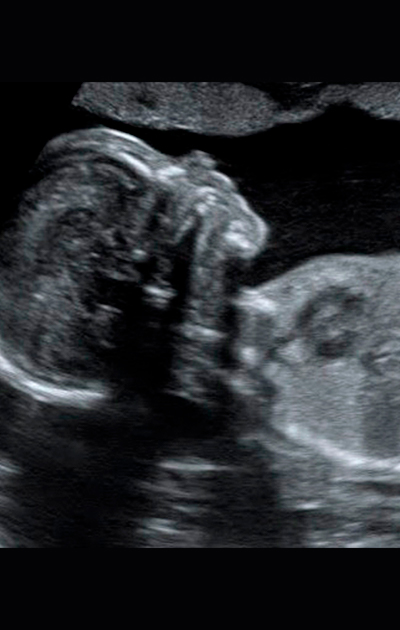

A Ultrassonografia ou ultrassom é um tipo de exame que produz imagens em movimento e em tempo real do feto e de estruturas do corpo. É importante ressaltar que não há radiação e o exame é totalmente seguro durante toda a gestação.

Ultrassons 3D ou 4D

Os ultrassons 3D ou 4D podem ser feitos durante o pré-natal de preferência entre as semanas 26 e 30 e são utilizados para ver detalhes físicos do bebê. O exame em 3D mostra detalhes do corpo do bebê, sendo possível ver o rosto e os órgãos genitais com mais nitidez, enquanto no exame em 4D, além das feições, também é possível visualizar os movimentos do feto na barriga da mãe em tempo real.